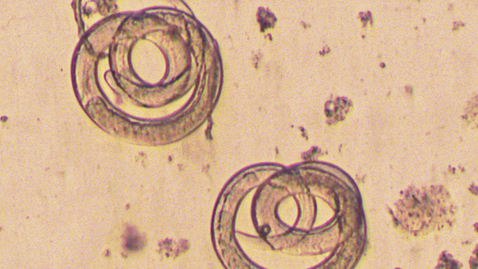

The type of lesion can be quite variable, but generally speaking, they start out as bumps, papules, and they can have a little indentation or dimple in the center of that papule. They can become pus-filled, and eventually, they scab over and they fall off, and they can leave a scar. They're fairly deep-seated, so they can be quite painful. And especially if they're in the mouth or genitals or the rectum, these places obviously can cause a lot of pain.

Dr. Swaminathan: Yeah, they usually progress or evolve. Like I said, they'll start out as a bump and then can become more liquid-filled, pus-filled, can become more painful, and they can break down so that they form an open sore. But eventually, they will scab and fall over. And this can take a couple of weeks or more for it to be fully cleared, and for the person then to not be infectious.